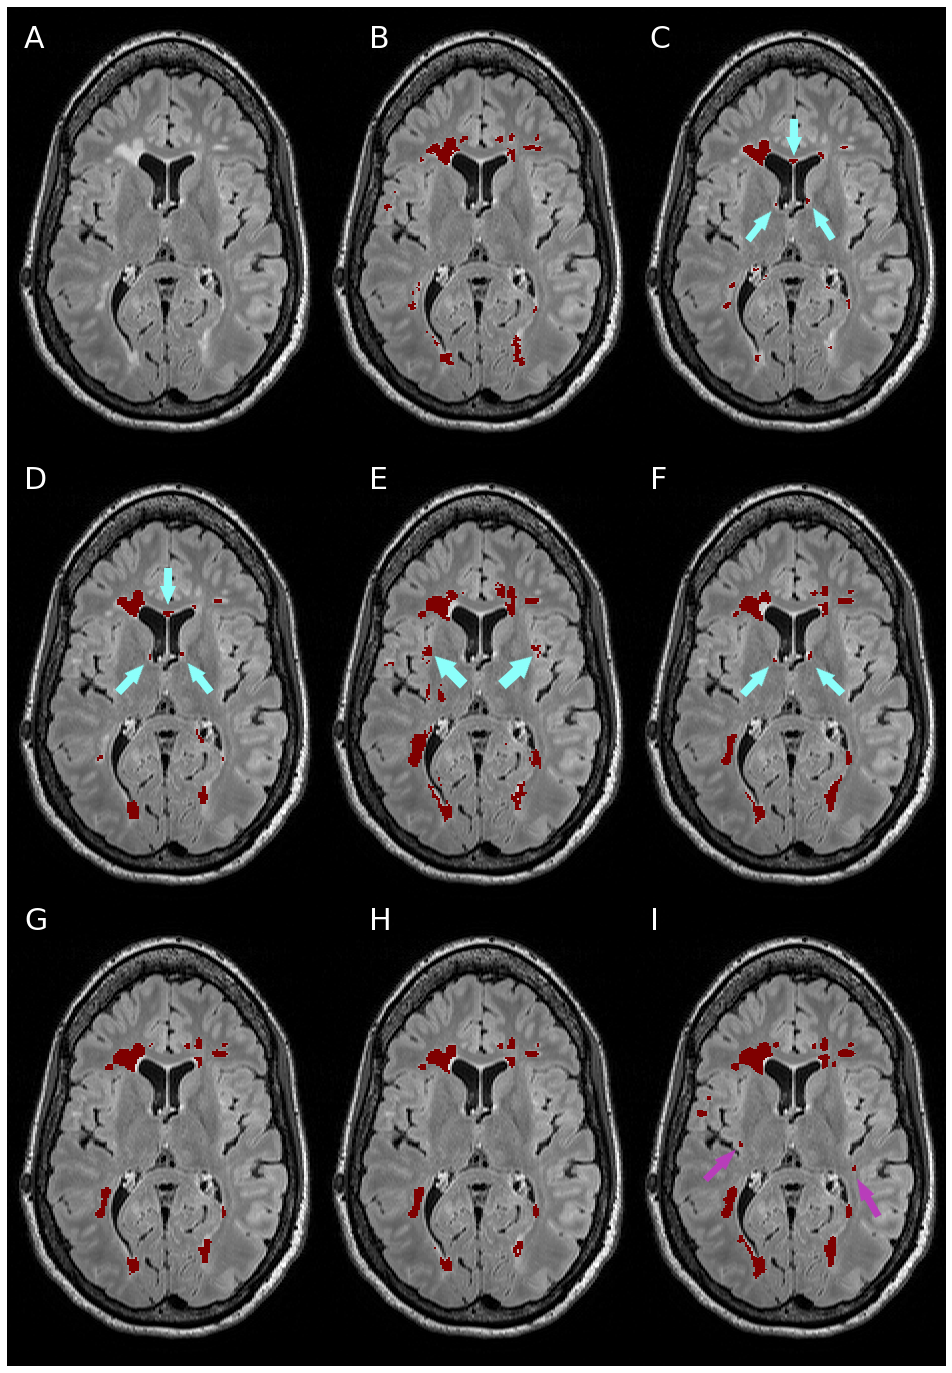

Performance metrics on the Insel32 dataset (vs the consensus segmentation) are summarised in Table 2, along with inter-rater comparison between the two raters, and between the raters and the consensus. An example of output of the methods considered, together with the manual ground truth, can be seen in Figure 2.

We performed Wilcoxon signed-rank tests of the differences between the methods, with a significance level of 0.05. All DeepSCAN and nnUnet models trained performed significantly better than LPA, LGA and nicMSlesions, according to both Dice coefficient and F1 score. No significant difference was found between the Dice coefficients of DeepSCAN (lesions only), DeepSCAN (lesions and brain structures) and nnUnet (lesions only): these three methods were significantly better regarding Dice coefficient than nnUnet (lesions and brain structures). Regarding lesion detection (lesion F1 score), DeepSCAN (lesions and brain structures) was significantly better than all other methods.